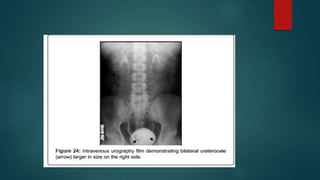

Chronic ureteritic cystica